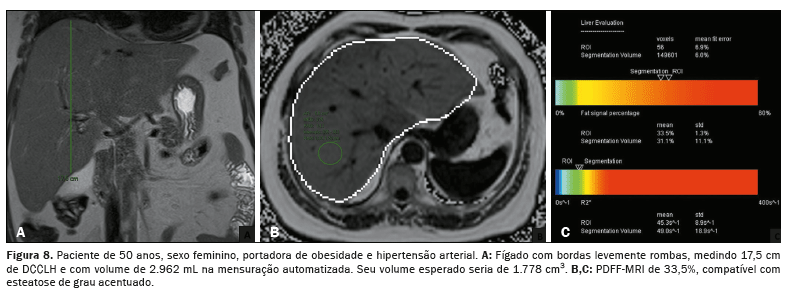

A associação, tanto do DCCLH e a PDFF-MRI (rs = 0,474;

p < 0,001) quanto da Voe e a PDFF-MRI (rs = 0,568;

p < 0,001), apresentou correlação estatisticamente significante, refletindo os resultados das análises anteriores (Figura 5). A relação entre o acúmulo de gordura e o aumento do volume hepático está exemplificada nas Figuras 6, 7 e 8.